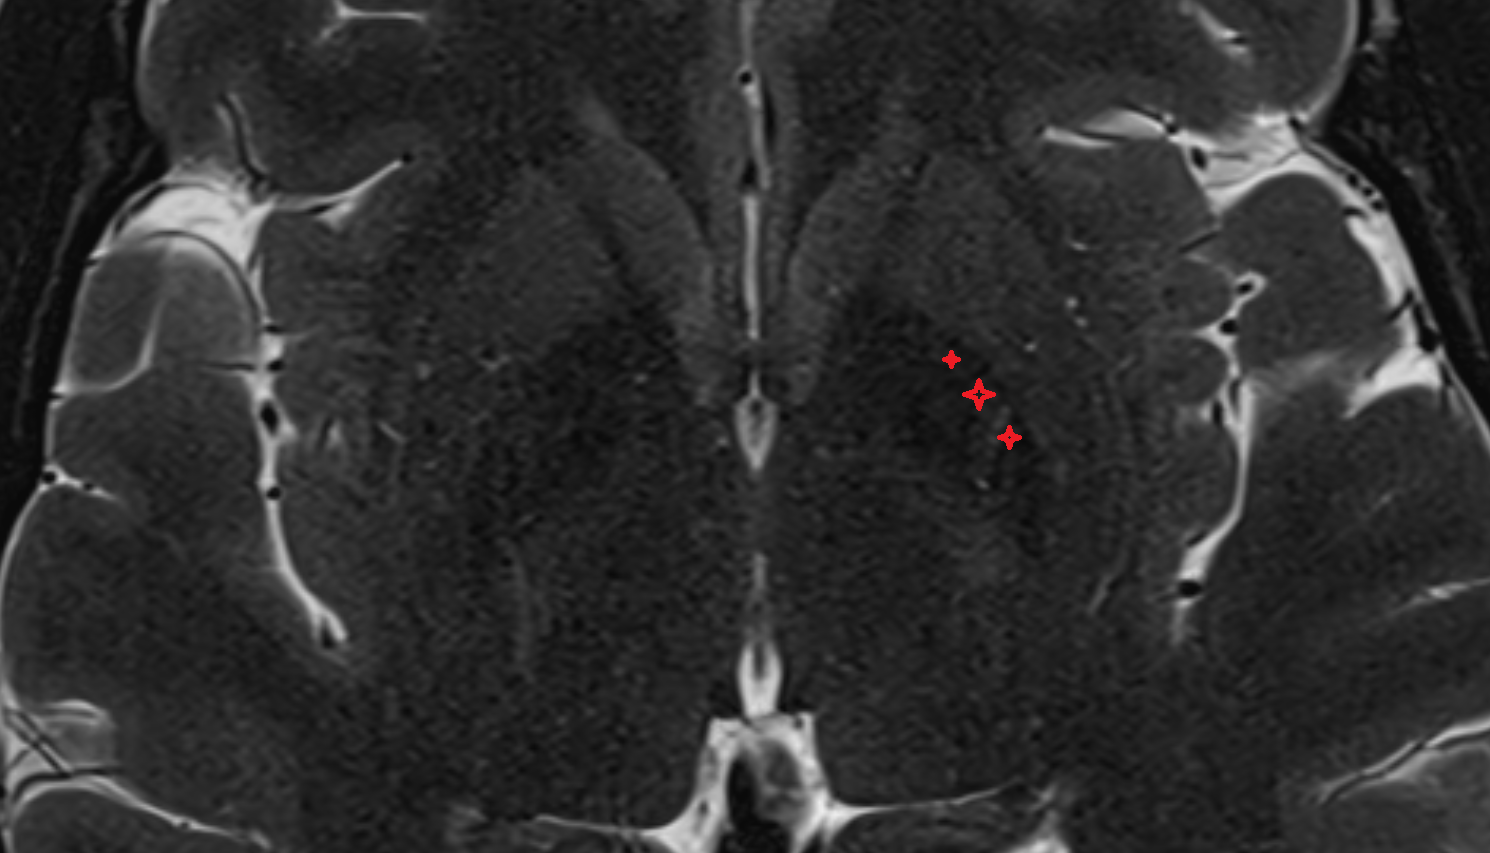

- Hippocampus